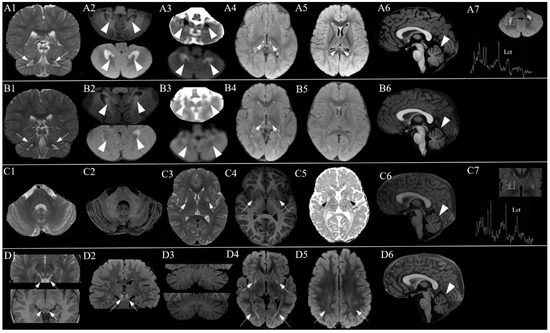

| Brain MRI | At the beginning, it was normal. At 3 months, new lesions in the cerebellar peduncles. At 7 months, brain atrophy, dentate nucleus lesions, and diffuse WM disease. | At 1 year, bilateral basal ganglia hyperintensity, mild brain atrophy. MRS showed lactate peak in basal ganglia. | Relapsing and remitting lesions hyperintense in T2, hypointense in T1 and with restricted diffusion in the acute phase in the peridentate WM, mesial nuclei of the thalami, CC splenium, lenticular nuclei and mesencephalic tegmentum. ↓ of grey/white matter contrast in the cerebellar hemispheres. ↑ lactate peak in the cerebellum and lenticular nuclei. |